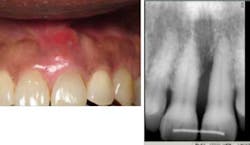

Case No. 3 — Mr. First Time

A 79-year-old African American male was diagnosed with chronic periodontitis. He had no prior dental care and presented with full dentition, no caries, and advanced bone loss with tooth mobility in molar areas. His chief complaint was a loose upper right tooth. The LANAP protocol was performed over two appointments with local anesthetic. Treatment was done in August 2012.

Mr. First Time before the LANAP protocol.